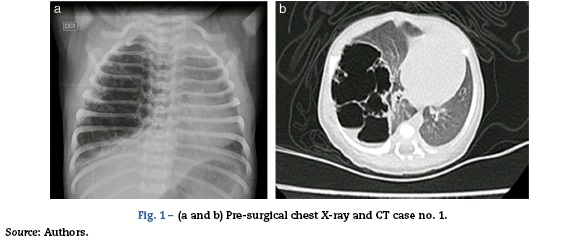

43-week post-conception age male patient with prenatal diagnosis of a right cystic adenomatoid malformation. At birth, the oxygen saturation ranged between 75 and 85%, requiring neonatal ICU admission. The birth weight was 3.2 kg. The pre-surgical paraclinical tests are described in Table 1. The ultrasound scan showed a patent foramen ovale, good biventricular function, mild pulmonary hypertension PSAP 35 mmHg. A CT scan is requested prior to the surgical procedure in order to characterize the lesion (Fig. 1a and b).

The pathology report of the right upper lobe indicated a Type II cystic adenomatoid malformation and the X-ray control showed adequate pulmonary expansion (Fig. 4).